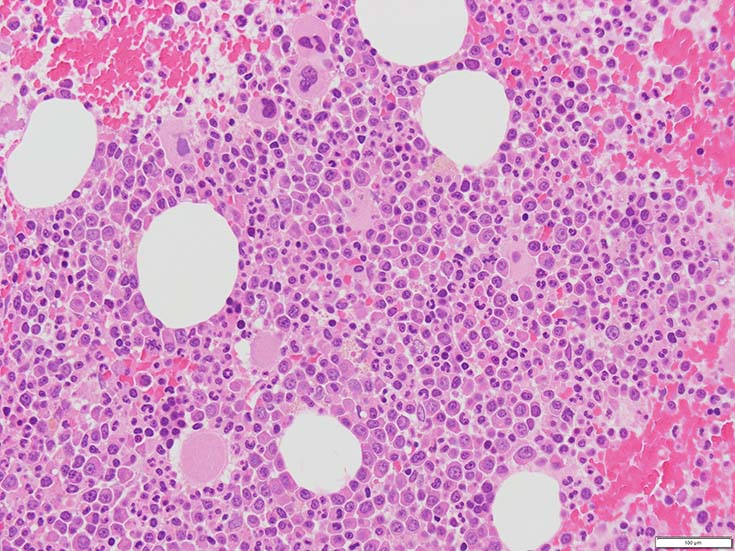

初診時の骨髄組織所見

thumb nail画像のクリックで大きな画像がみられます.

HE染色および, Naphtol-ASD-CAE染色した骨髄クロット組織標本-->Naphtol-ASD-CAE染色, 載せガラス法のページをみる.

70-80%のhypercellular marrow. 3系統造血細胞が認められる. Naphtol-ASD-CAE染色で赤色にそまる顆粒球系細胞増生が顕著な骨髄組織.

promyelocytesなど幼若顆粒球系細胞の集簇がみられるが, 分葉好中球他, 成熟顆粒球(Naphtol-ASD-CAE染色は薄く染まる傾向あり)も多く認められacute leukaemiaの所見ではない.

単球(Naphtol-ASD-CAE染色陰性)が密に増殖する所見は骨髄組織には認められない(*1)